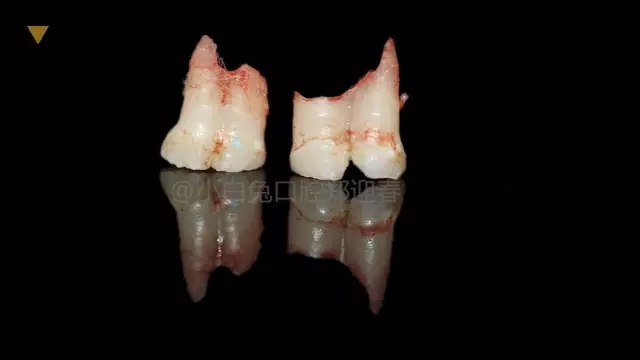

患兒,10歲,因上前牙未替換來診,查體:輕度反合,51和52、61和62均融合,且存在間隙約4mm,全面曲面斷層片顯示:11、21未萌,52、51、61、62牙根均有不同程度的生理性吸收。

拔出后的離體牙